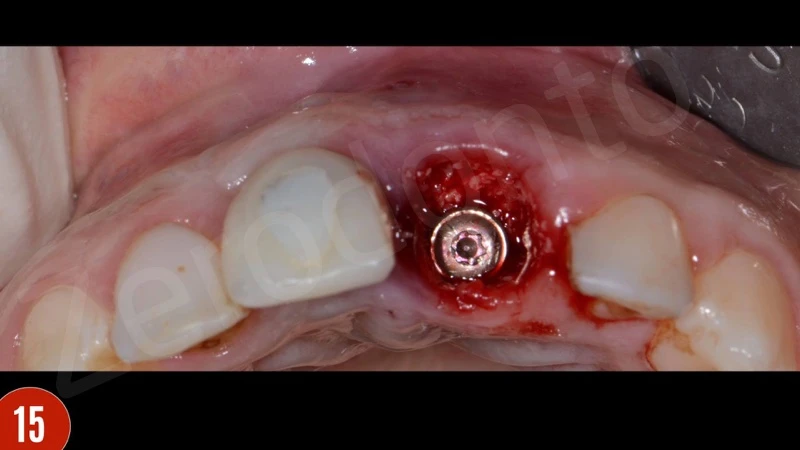

Sau khi nhổ răng, mô hạt đã được loại bỏ cẩn thận. Khoan xương phía khẩu cái cung cấp sự ổn định chính và đặt phục hình tạm thời. Để bảo vệ các đường cong phía môi, khoảng trống giữa bản xương phía môi và implant được ghép với xương bò khử khoáng. Phục hình tạm thời được gắn vào implant tại lực torque 15 Ncm.